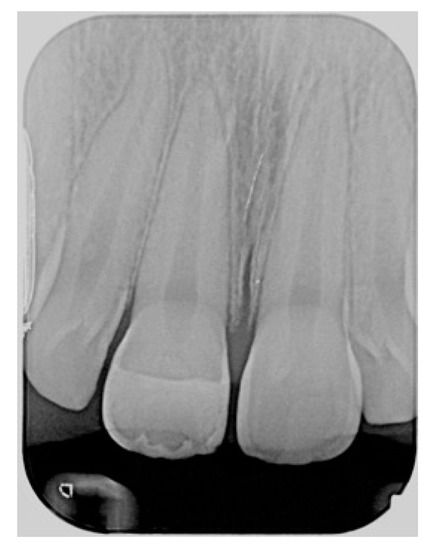

Finishing and polishing procedures were performed with a diamond bur (WL 268 014 Horico, Berlin, Germany), silicone points (Identoflex, Kerr, Bioggio, Switzerland) brushes (Jiffy Goat Air Brushes, Ultradent Products, South Jordan, UT, USA), and diamond pastes (Diamond Polish Mint, Ultradent Products, South Jordan, UT, USA) (Figure 13 and Figure 14). Satisfactory clinical and radiographic outcome was considered satisfactory at 3-months, 1-year, and 5-years post-operative (Figure 15, Figure 16, Figure 17, Figure 18 and Figure 19).

Figure 19.

Five years post-operative x-ray.